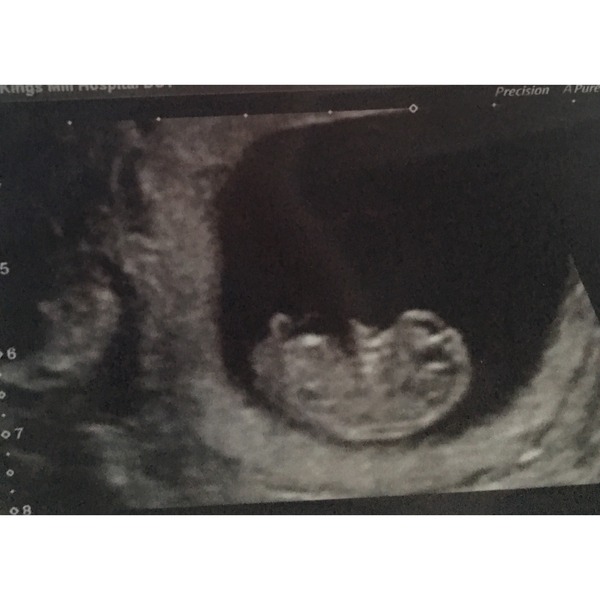

Met with the midwife for the first time and she found a heartbeat, so guessed I was around the 12 week mark, however when I went to the scan was only 10 weeks, the second scan I had in EPU after having gone to A&E with severe abdominal pain for about 3 days?, which turned out to be nothing serious - guess I just panicked because I don't really know what to expect as normal throughout a pregnancy, worried me slightly, and the third is my dating scan.